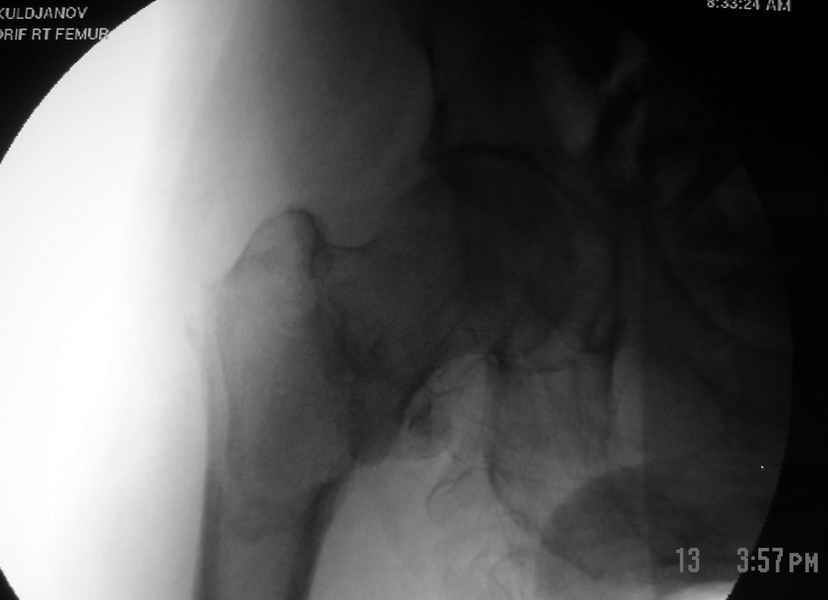

Как раз недавно у меня был примерный случай: больному 36 лет, поступил ночью, травма в результате мотоциклетной аварии, кроме чрезвертельного и спирального перелома левого бедра имеется переломы костей предплечья с этой же стороны. Скелетное вытяжение, а на следующий день больной про оперирован на ортопедическом столе с дистракцией. Чтобы не расколоть чрезвертельный перелом провели временную спицу ближе к переднему кортексу, из малого разреза костодержатель для репозиции, а фиксацию провели антиградным штифтом. Этапы операции на снимках.

Джолдас Кульджанов

Djoldas Kuldjanov, MD

Department of Orthopedic Surgery

St. Louis University Medical Center